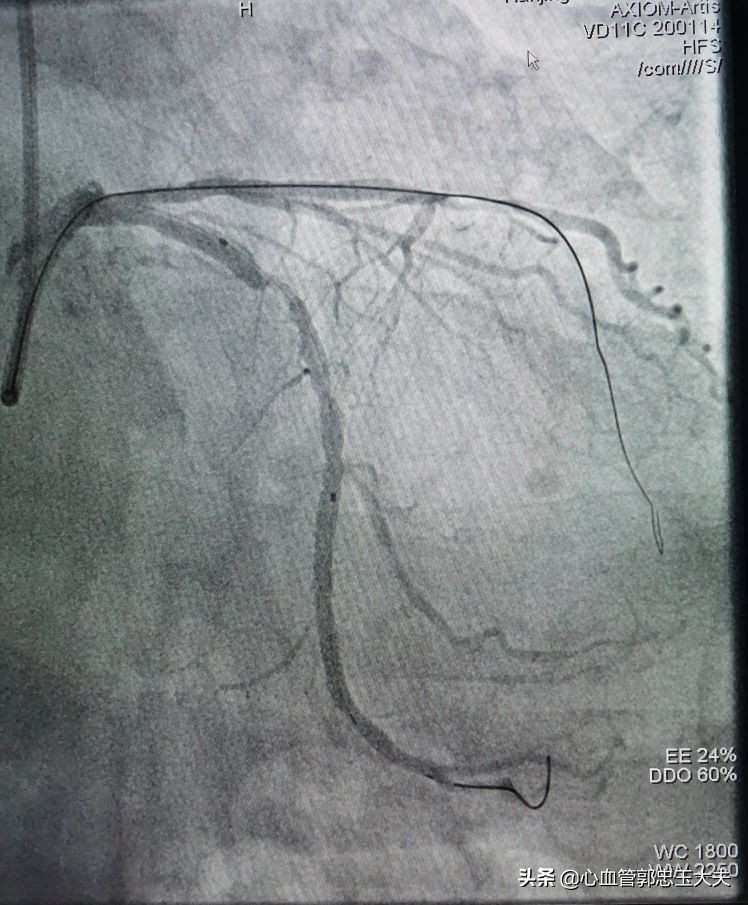

回旋支近段远端85~90%狭窄(如下图)

手术策略:计划先开通前降支中远段闭塞段,术*考前**虑到中远段完全闭塞合并钙化,因此开通难度特别大,也跟家属做了充分沟通。EBU大腔到位,回旋支BMW导丝到位加强支撑。FielderXT及Pilot50及150通过困难,反复尝试,FielderXT终于通过闭塞段。如下图

1.5*15mm微球囊通过病变血管困难,在回旋支预埋球囊,扩张加强支撑,微球囊仍然难以通过闭塞病变(如下图)